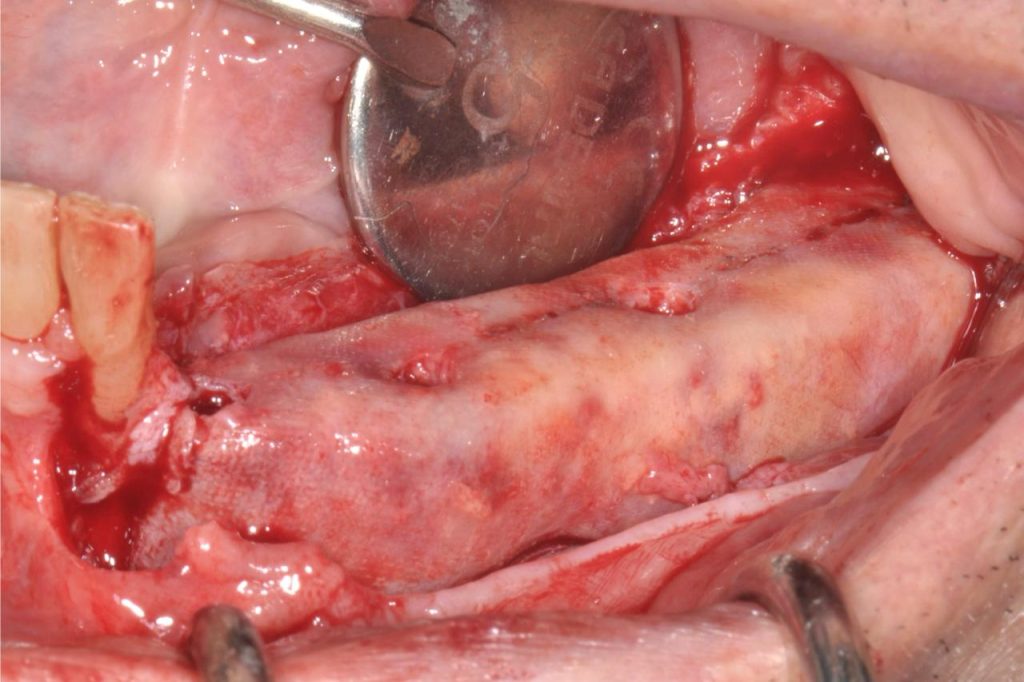

- Mesh customizzate di nuova generazione: campi d’applicazione, potenzialità, strategia di fissaggio, prospettive e futuro, modalità di rimozione

- Gestione dei tessuti molli post GBR